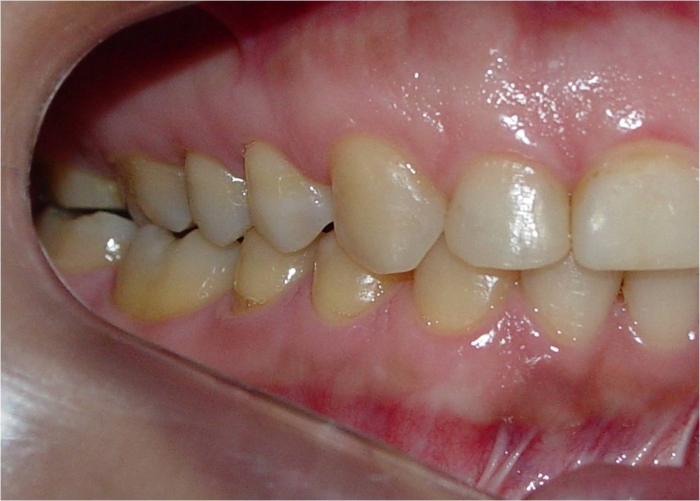

Mordida inicial